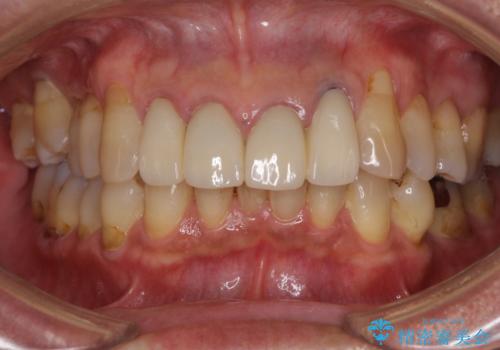

前歯のセラミッククラウンを装着したばかりであったので、根管治療のためにクラウンを壊さなければならないことを残念に思っていらっしゃいました。

しかし、根管治療後はすぐに痛みがひき、治療を受けられて良かったとのことでした。